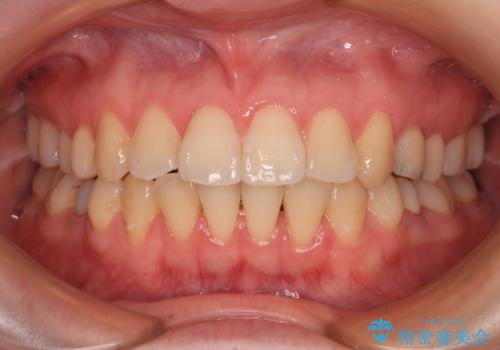

開咬と前方に飛び出した前歯 インビザラインによる矯正治療

- 上下前歯の非接触と叢生を気にして来院された患者様です。

開咬の改善はインビザラインの最も得意とするところであるため、インビザラインを用いて矯正治療を行うこととしました。

舌の突出癖改善のトレーニングをしっかりと行っていただき、上下前歯が接触する咬み合わせを達成することができました。